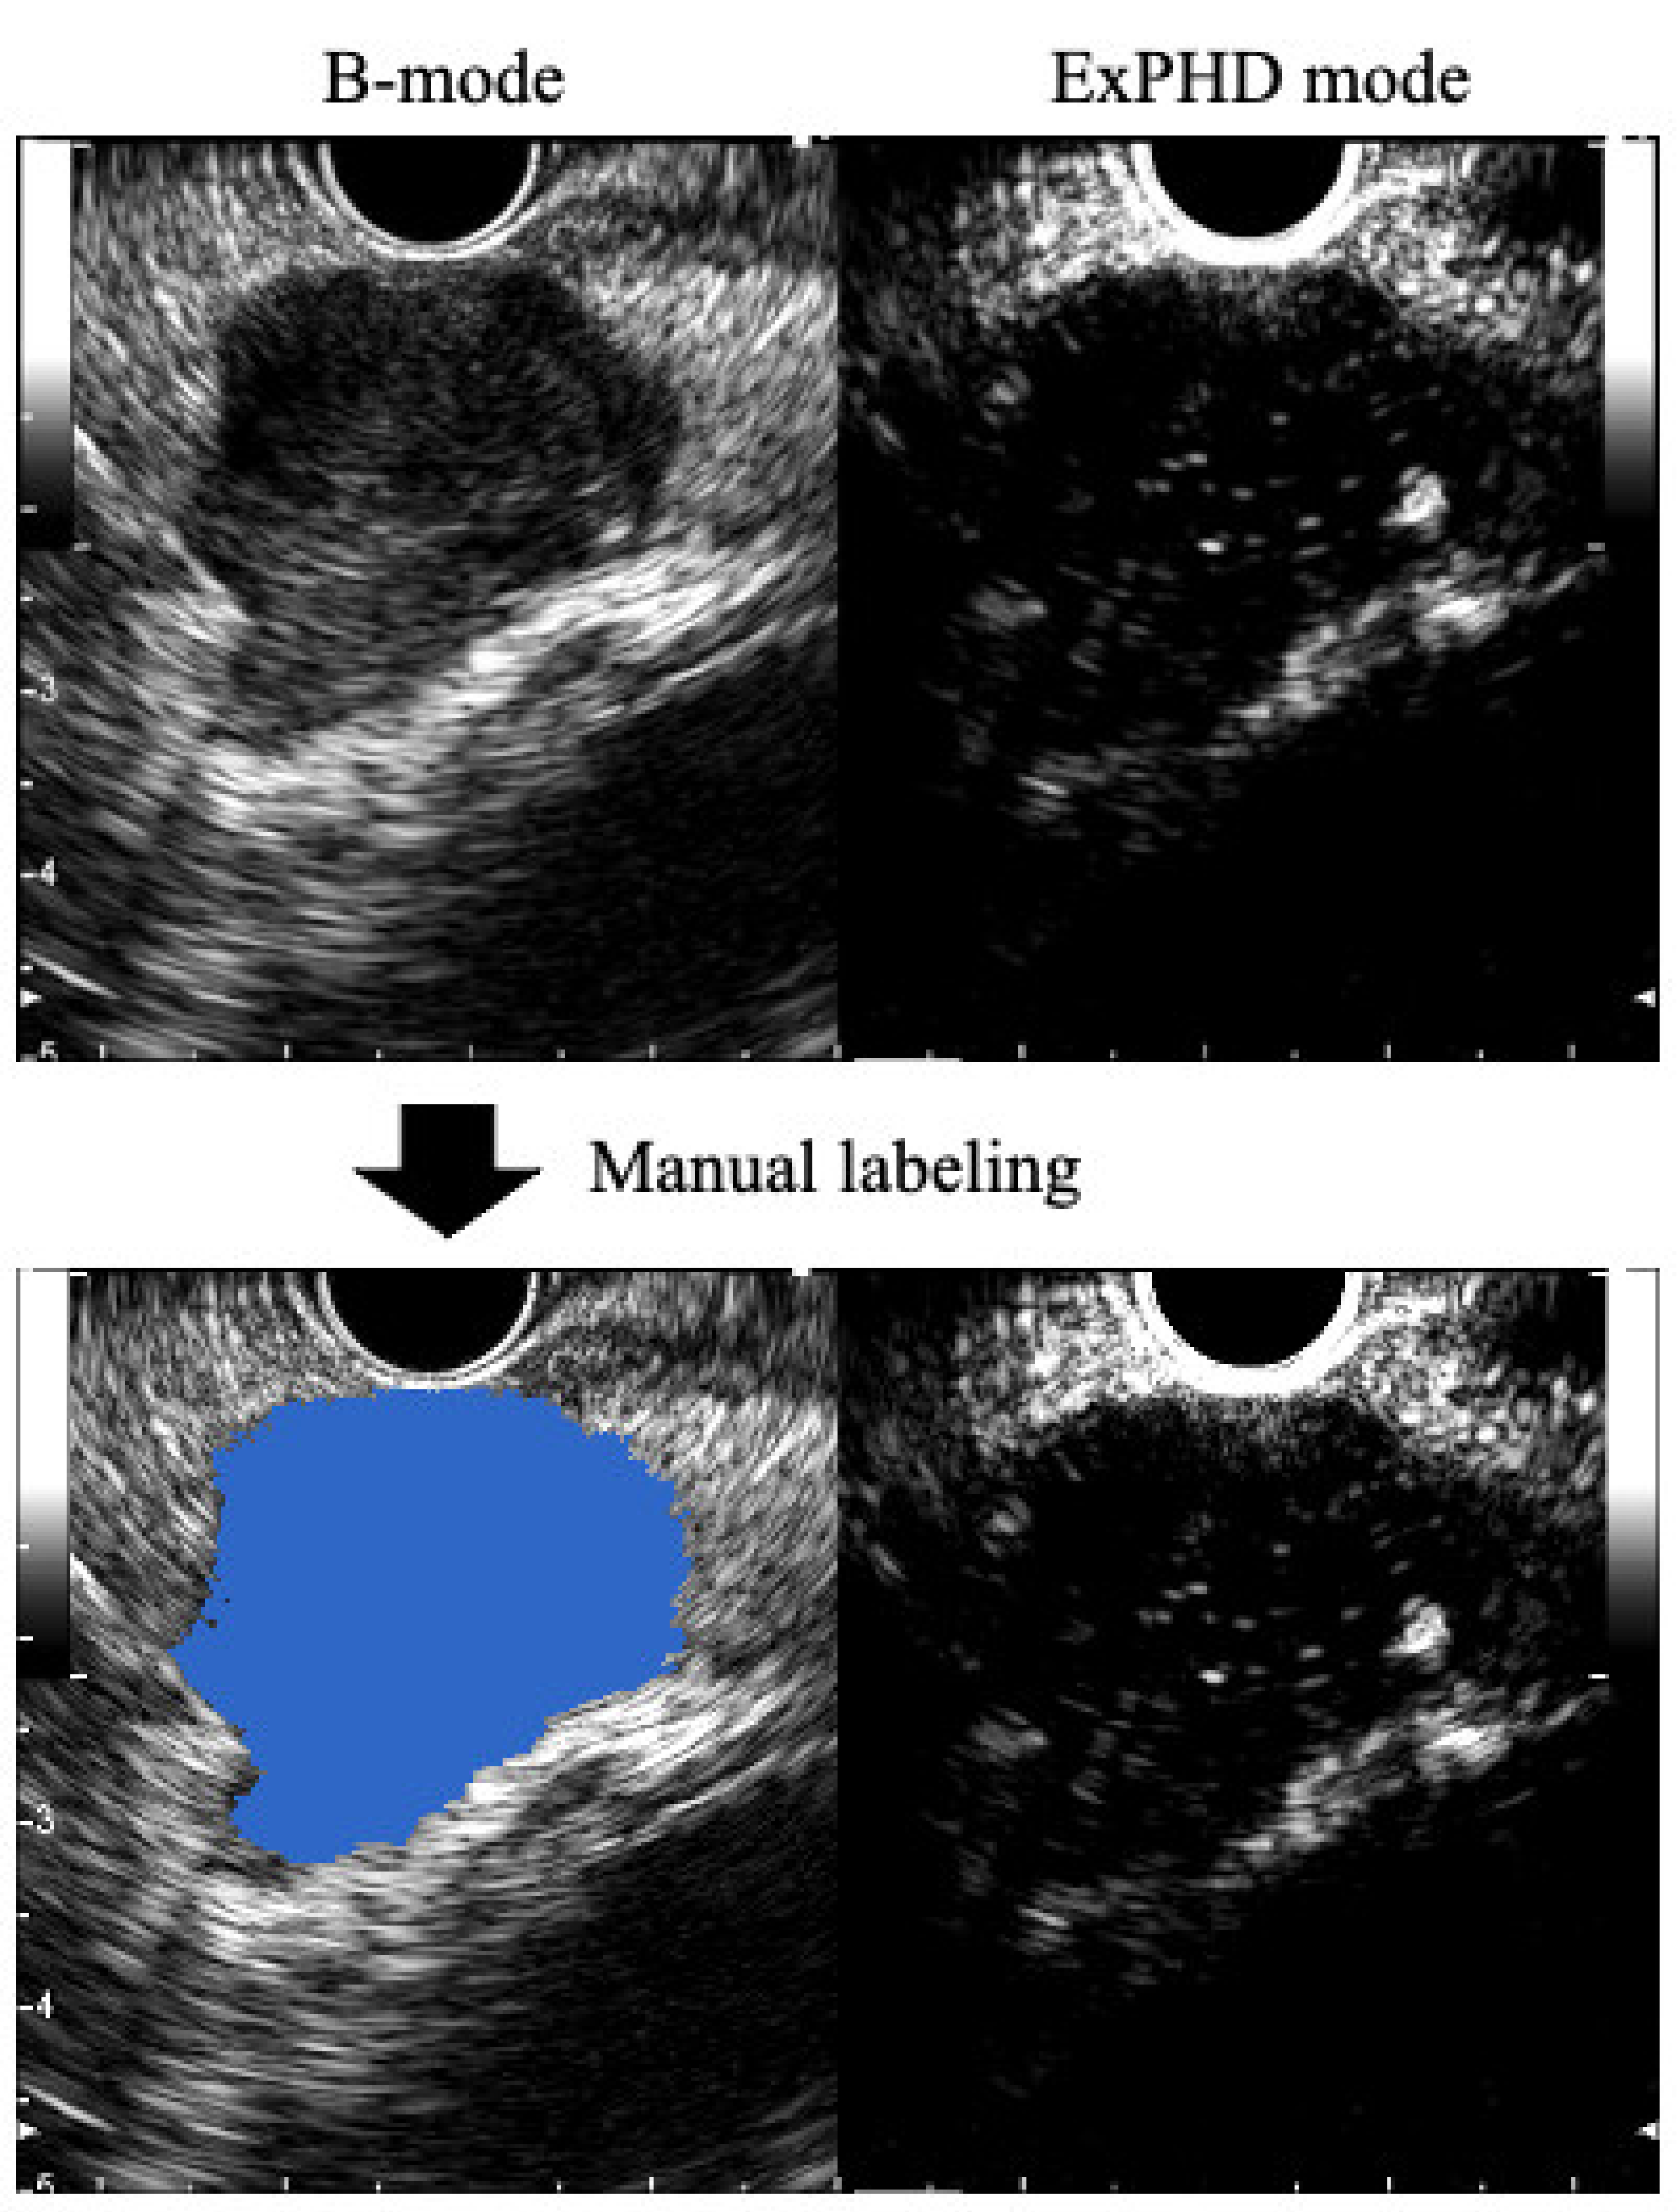

2.3. Preparation of the Training Data Sets